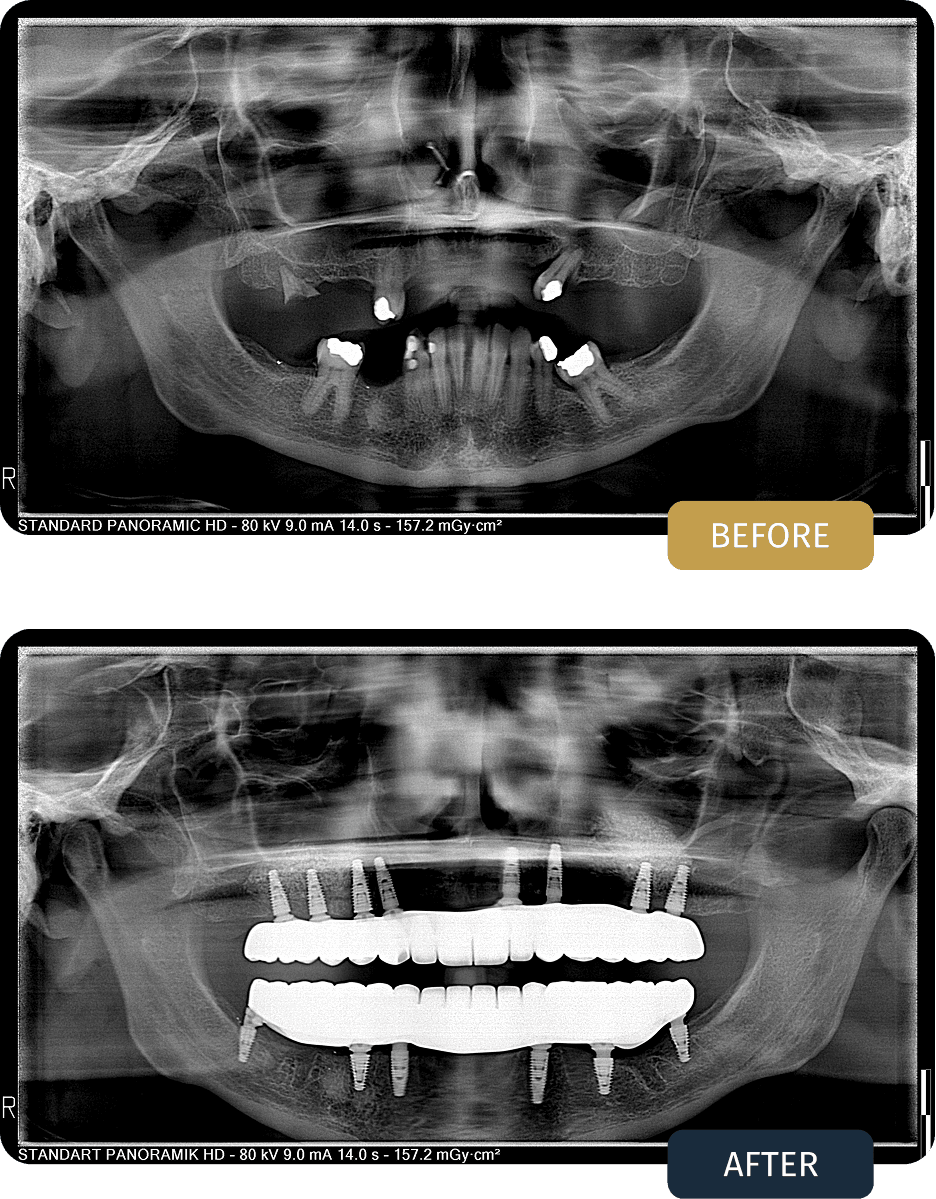

Clinical examination and panoramic imaging revealed advanced bone loss in the upper jaw, with insufficient bone volume to safely place dental implants without additional surgical intervention. The sinus cavities had expanded into the implant zones, making standard implant placement impossible without sinus lifting and bone grafting procedures.

The lower jaw also showed compromised dentition, indicating the need for a full arch, implant supported solution to restore long term function and stability.

Laura underwent a comprehensive treatment plan beginning with sinus lifting surgery and bone grafting in the upper jaw. This procedure restored sufficient bone volume and created a stable foundation for secure implant placement and long term success.

After the healing and stabilization phase, an All on 8 implant treatment was performed on the upper jaw and an All on 6 implant treatment on the lower jaw. Titanium bar frameworks were used to provide maximum strength, stability, and even distribution of chewing forces.